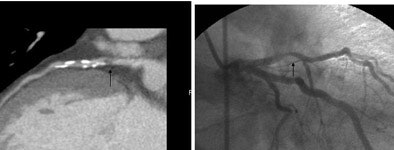

![]() |

| Coronary artery bypass grafts visualized on 64-slice CTA scan. All images courtesy of Dr. David Dowe. |